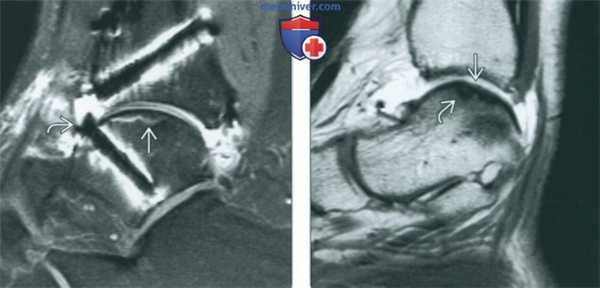

(Слева) МР-артрография в режиме PD FSE FS, сагиттальный срез: в большеберцовой и таранной костях видны костно-хрящевые аллотрансплантаты. Заметна небольшая зона аваскулярного некроза. Головка винта выступает за суставной хрящ таранной кости. После удаления винта боли исчезли.

(Справа) МР-артрография в режиме Т1ВИ, сагиттальный срез: отмечается ровный контур фиброзного хряща, заполнившего коано-хрящевой дефект после высверливающей хондропластики. Зона реактивного склероза в подлежащей кости при всех последовательноаях характеризовалась гипоинтенсивным сигналом.

(Слева) МР-артрография в режиме Т1ВИ FS, аксиальный срез: визуализируется костно-хрящевой фрагмент (2 стадия). Отсутствие жидкости вокруг фрагмента свидетельствует о стабильности. При дефекте таранной кости почти всегда выявляется разрыв передней таранно-малоберцовой связки.

(Справа) МРТ в режиме Т2ВИ FS, коронарный срез: виден затек жидкости под костно-хрящевой фрагмент таранной кости, что указывает как минимум на неполное его отслоение. Следует отметить истончение суставного хряща. (Слева) МР-артрография в режиме Т2ВИ FSE FS, сагиттальный срез: визуализируется затек контрастного препарата под небольшой костно-хрящевой фрагмент, что соответствует 3 стадии.